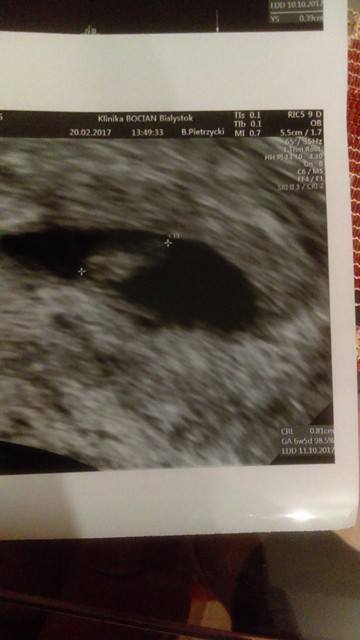

No to jestem po wizycie, serduszko już bije

byłam prywatnie i ginekolog, który jest bardzo znany i bardzo dobry, powiedział abym odstawiła duphaston, ponieważ on może u mnie wywoływać takie masakryczne mdłości, przez które nie spię całą noc, podobno za dużo progesteronu to powoduje, ufam mu i będę prowadzić jednak u niego ciąże, tabletki kazał odstawić także nie będę już brała i wtedy zobaczymy, niestety te ciałko żólte-torbiel ma już 6 cm, ciągle rośnie, ale lekarz mnie uspokajał że się wchłonie i następna wizyta 20 marca. Ciąża ma 6tyg5dni

robaczek ma

8.1 mm